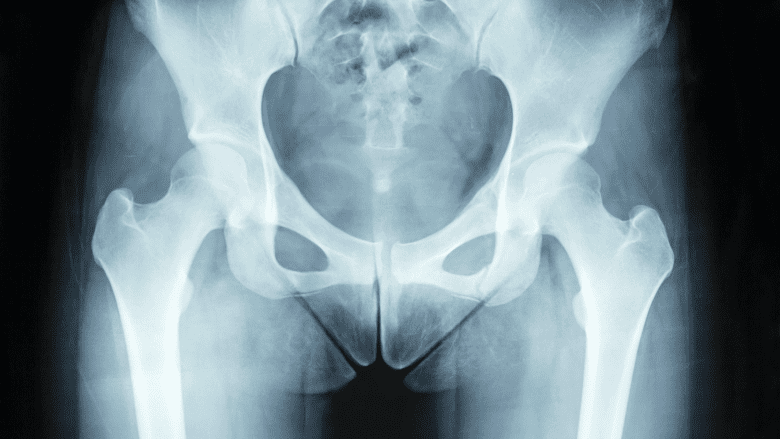

2. Diagnostic imaging

X-ray or ultrasound are typically used initially, based on the doctor’s probable suspected diagnosis. Magnetic resonance imaging (MRI) is frequently necessary to diagnose soft tissue groin injuries and some stress fractures.